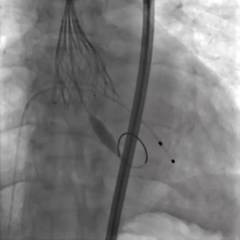

手术过程

造影及超声均可见主动脉瓣大量反流

无窦侧0位起始,最终释放深度满意

多角度评估位置合适,无瓣周漏

瓣膜释放后无位移,锚定牢固